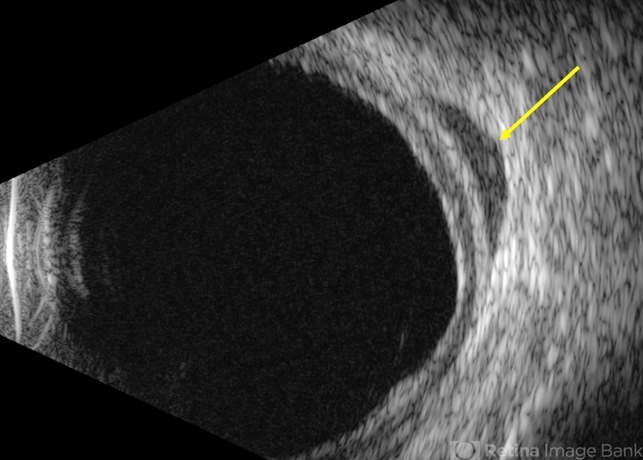

- Uveal lymphoma

- B-scan echography (T10) shows a hypo-echoic mass posterior to the globe consistent with orbital involvement of uveal lymphoma.